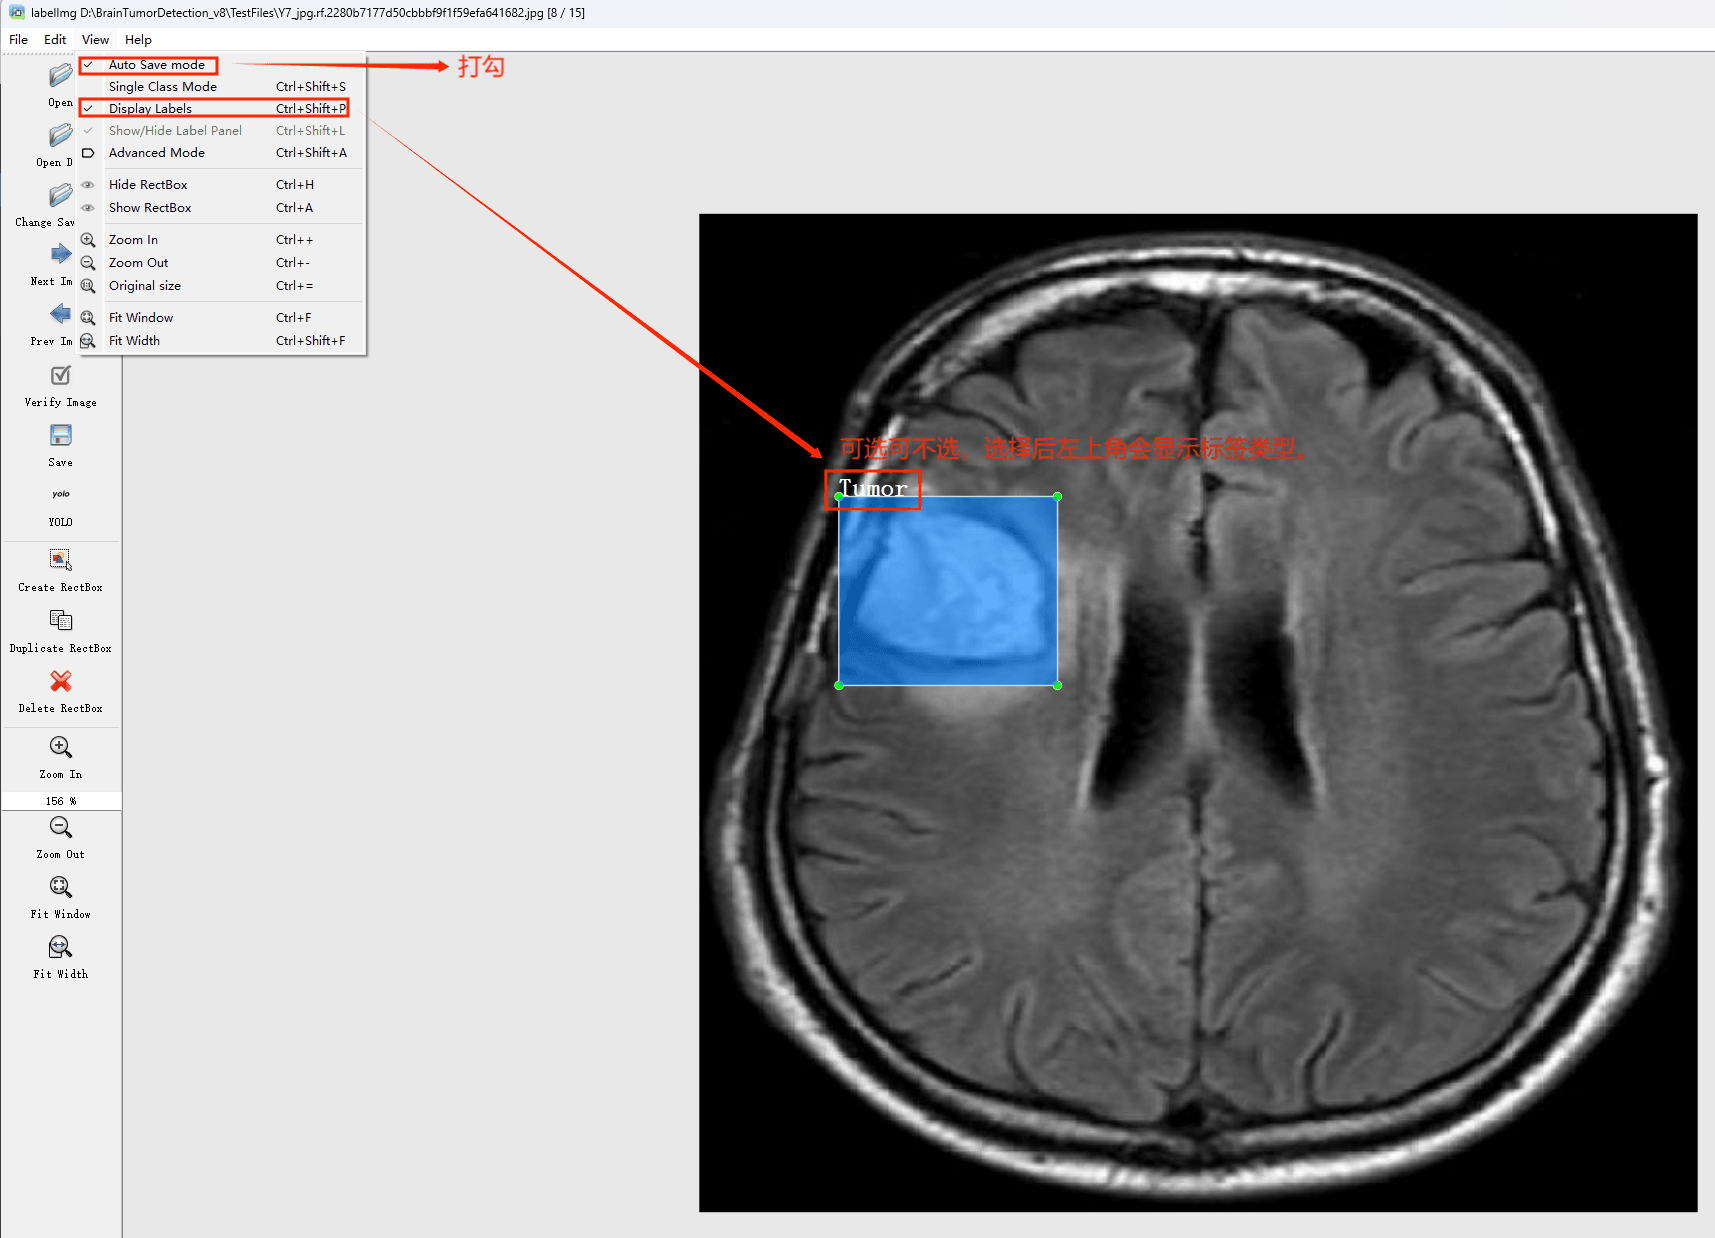

(1)labelimg:开源的图像标注工具,标签可用于分类和目标检测,它是用python写的,并使用Qt作为其图形界面,简单好用(虽然是英文版的)。其注释以 PASCAL VOC格式保存为XML文件,这是ImageNet使用的格式。此外,它还支持 COCO数据集格式。

初识labelimg

打开后,我们自己设置一下

在View中勾选Auto Save mode

接下来我们打开需要标注的图片文件夹

并设置标注文件保存的目录(上图中的Change Save Dir)

接下来就开始标注,画框,标记目标的label,然后d切换到下一张继续标注,不断重复重复。